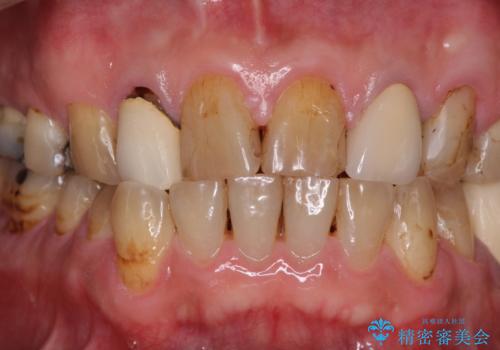

- コンポジットレジンやクラウンなど、様々な医院で治療を受けたために、統一感がなくなってしまった前歯を綺麗にしたいとのことで来院された患者様です。

黄ばんだ前歯や白すぎたクラウン、プラスチックの継ぎ接ぎなどを全てオールセラミッククラウンの統一感のある前歯に仕上げました。